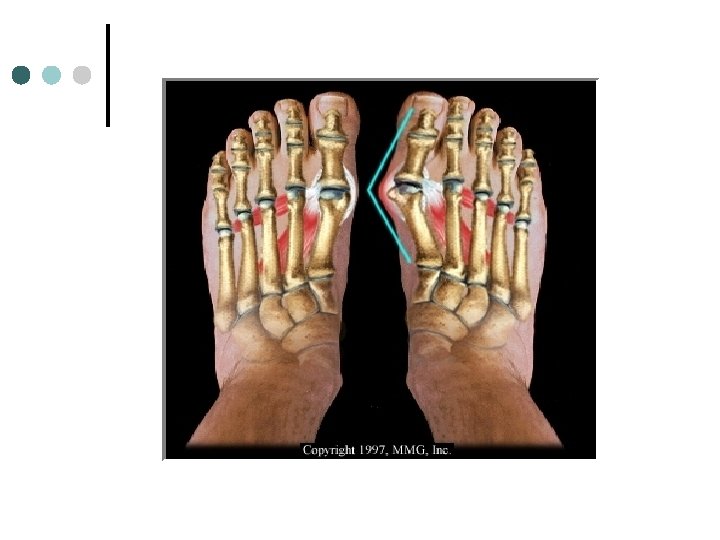

Bunion Cause: Bony enlargement of the head of the 1 st metatarsal caused from wearing improperly fitting shoes. ¢ S/S: Obvious deformity, tenderness, and swelling. ¢ TX: Proper shoe selection, protection devices, surgery may be necessary ¢ Prevention: Properly fitting shoes. ¢